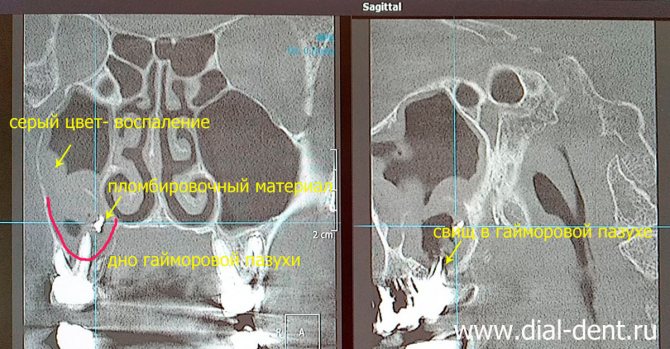

Для подтверждения диагноза и при подозрении на давнее повреждение используют:

- рентген верхнечелюстных пустот;

- компьютерную томографию челюстно-лицевой области;

- У части больных корни верхних зубов внедряются в полость пазухи. При удалении зубов автоматически происходит нарушение целостности костной пластинки. При лечении возможно попадание материала для пломбирования в полость.

Вероятность перфорации пазухи увеличивается при расположении зубного корня в непосредственной близости к ней в момент удаления. Поэтому хирургическое лечение должно проводиться с предельной аккуратностью и последующим рентгенологическими контролем состояния тканей после операции. Также стоматолог контролирует состояние тканей при использовании штифтов для имплантации или при обработке корневых каналов в целях пломбирования, так как велик риск проникновения материала пломбы и обломков корня в гайморову пазуху.

Ощутимую помощь окажет рентген носовых пазух. Если на плёнке видны затемнения в полости, значит, налицо скопление крови внутри. Также на снимке удаётся рассмотреть обломки корней зуба, расположение штифтов, торчащий материал внутриканальной пломбы. Развеять сомнения поможет рентгенография с использованием контраста.

Недостаток рентгена – в его двумерности. Стереоизображение легко получить при прохождении компьютерной томографии. Врач рассмотрит результат сканирования в специальной программе, изучит зуб со всех сторон и выберет план лечения.